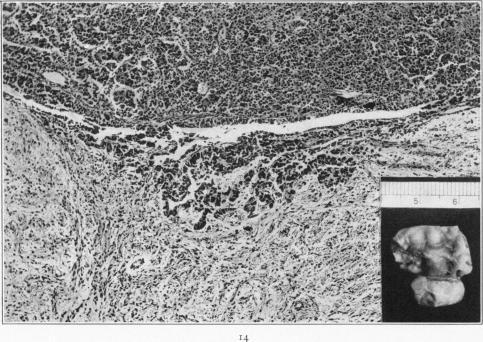

Hyperactivation of the Neurohypophysis as the Pathological Basis of Eclampsia and Other Hypertensive States.

Am J Pathol. 1934 Mar;10(2):145-176.31.

Hyperactivation of the Neurohypophysis as the Pathological Basis of Eclampsia and Other Hypertensive States.神经垂体的过度激活作为子痫及其他高血压状态的病理基础